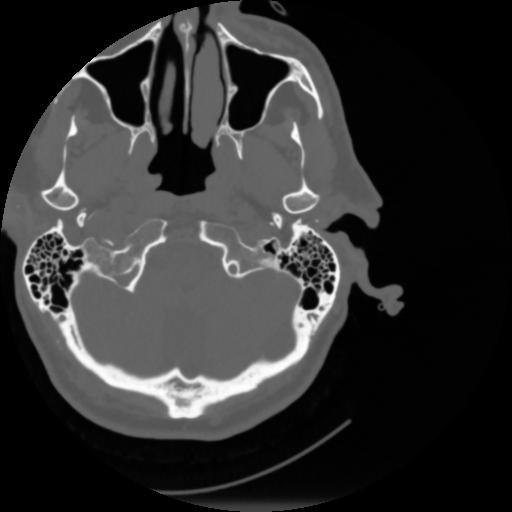

4 CEREBRO,,Vol,0.5,CEREBRO,,